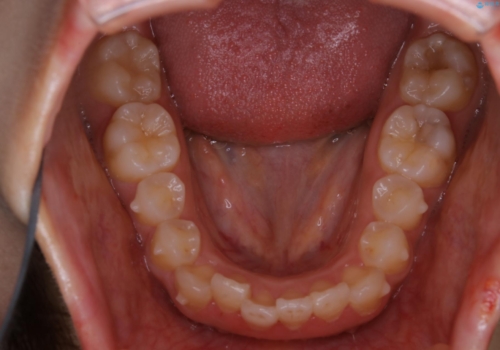

- 治療計画

- 4年ほど前から地元の歯科医院にてインビザライン治療を行っていたが、引っ越し後に通いづらくなってしまったため、治療が途中で止まってしまっているとの事で来院されました。性格的にインビザラインの継続した使用が難しいとのことで、ワイヤー装置にて最終仕上げを行いました。

インビザラインは20時間以上の装着を厳守して頂くことで治療効果が期待できる治療となります。固定式のワイヤー装置に切り替えることで短期間で歯並びを整えることができ、大変喜んでいただけました。